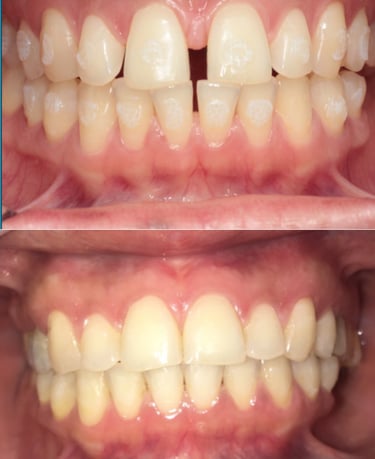

EVOLUÇÃO